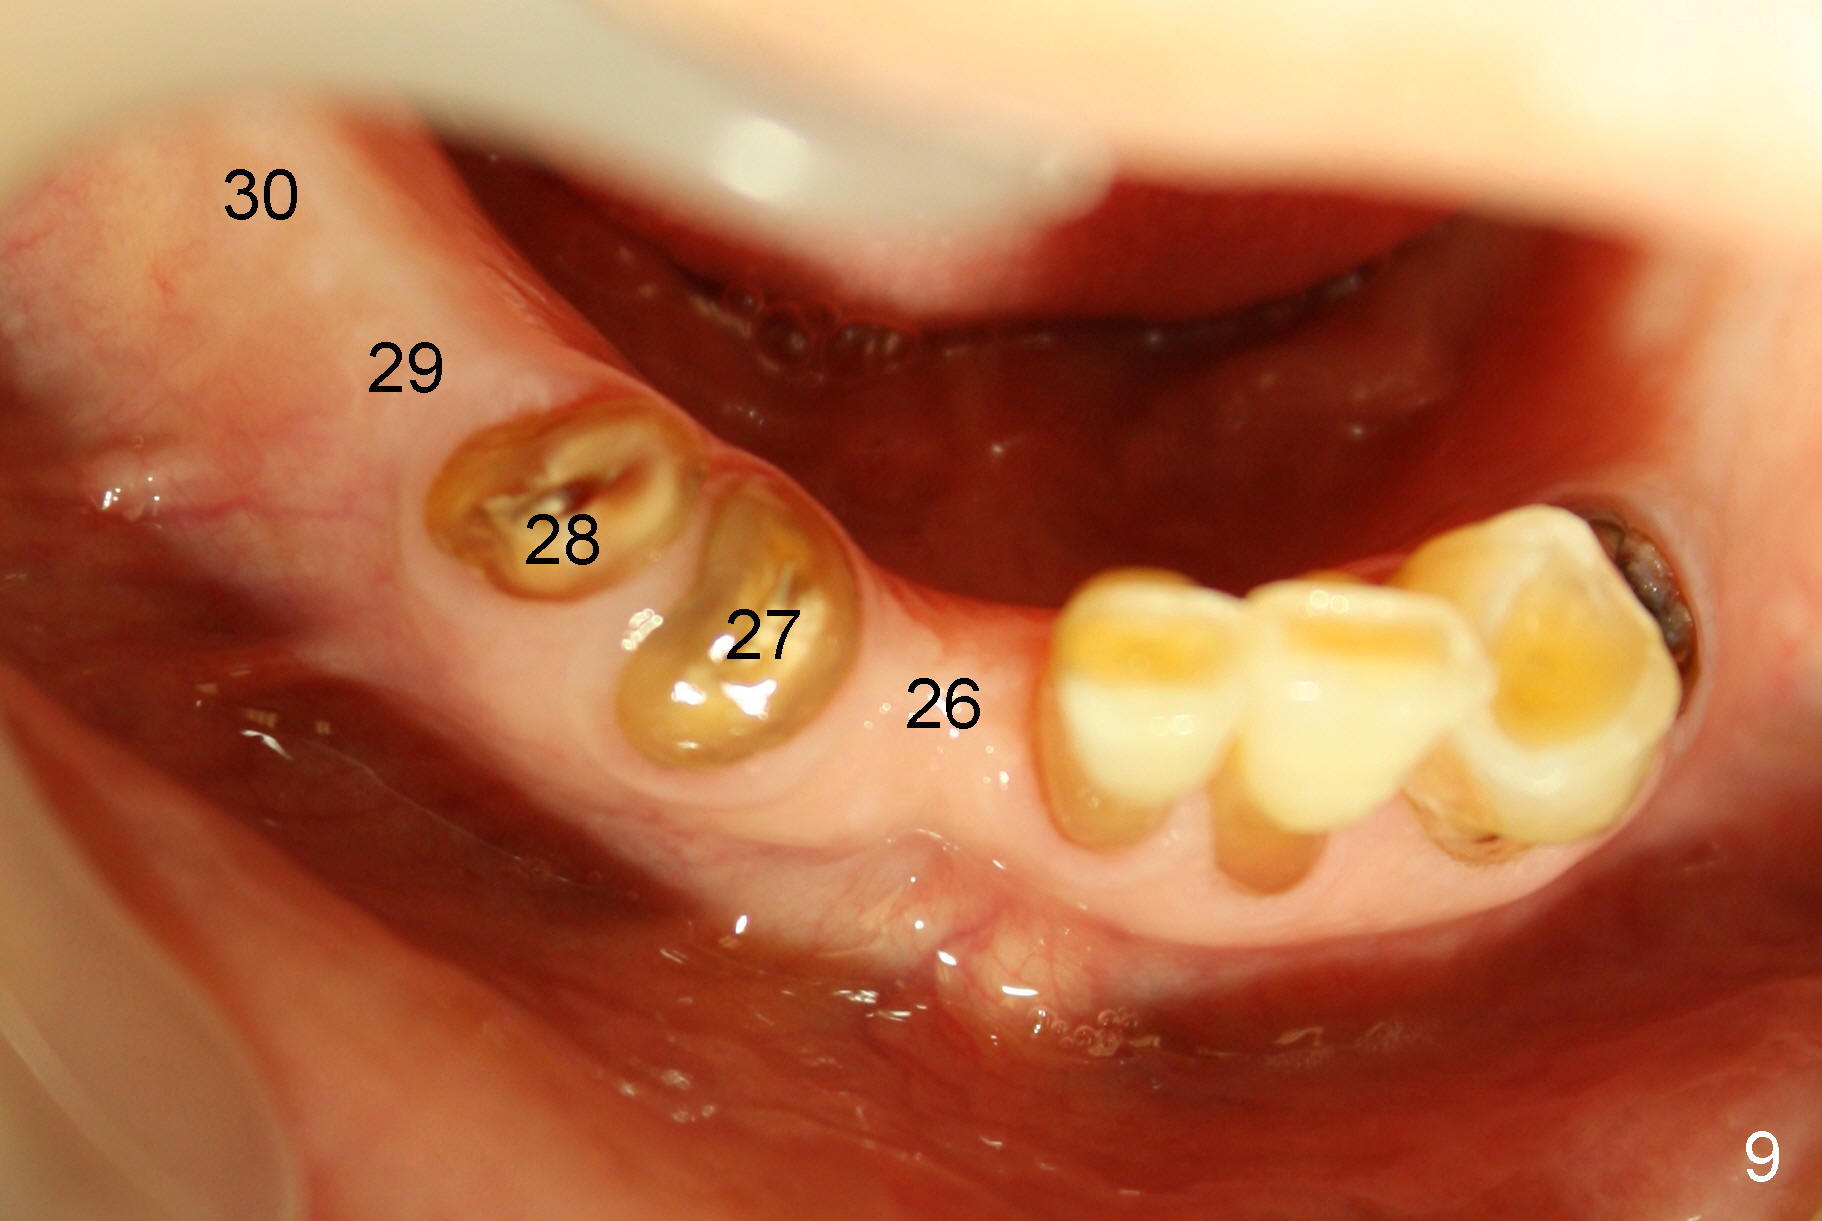

A 85-year-old man has poor dentition (Fig.9). Multiple implants are to be placed at one or two stages (#26-30). If primary stability is obtained for individual implants, they are splinted and immediate provisional is fabricated.

The sockets of #27,28 will be treated with 2% Xylocaine/1.:50,000 Epinephrine as control group of the antibiotic study.